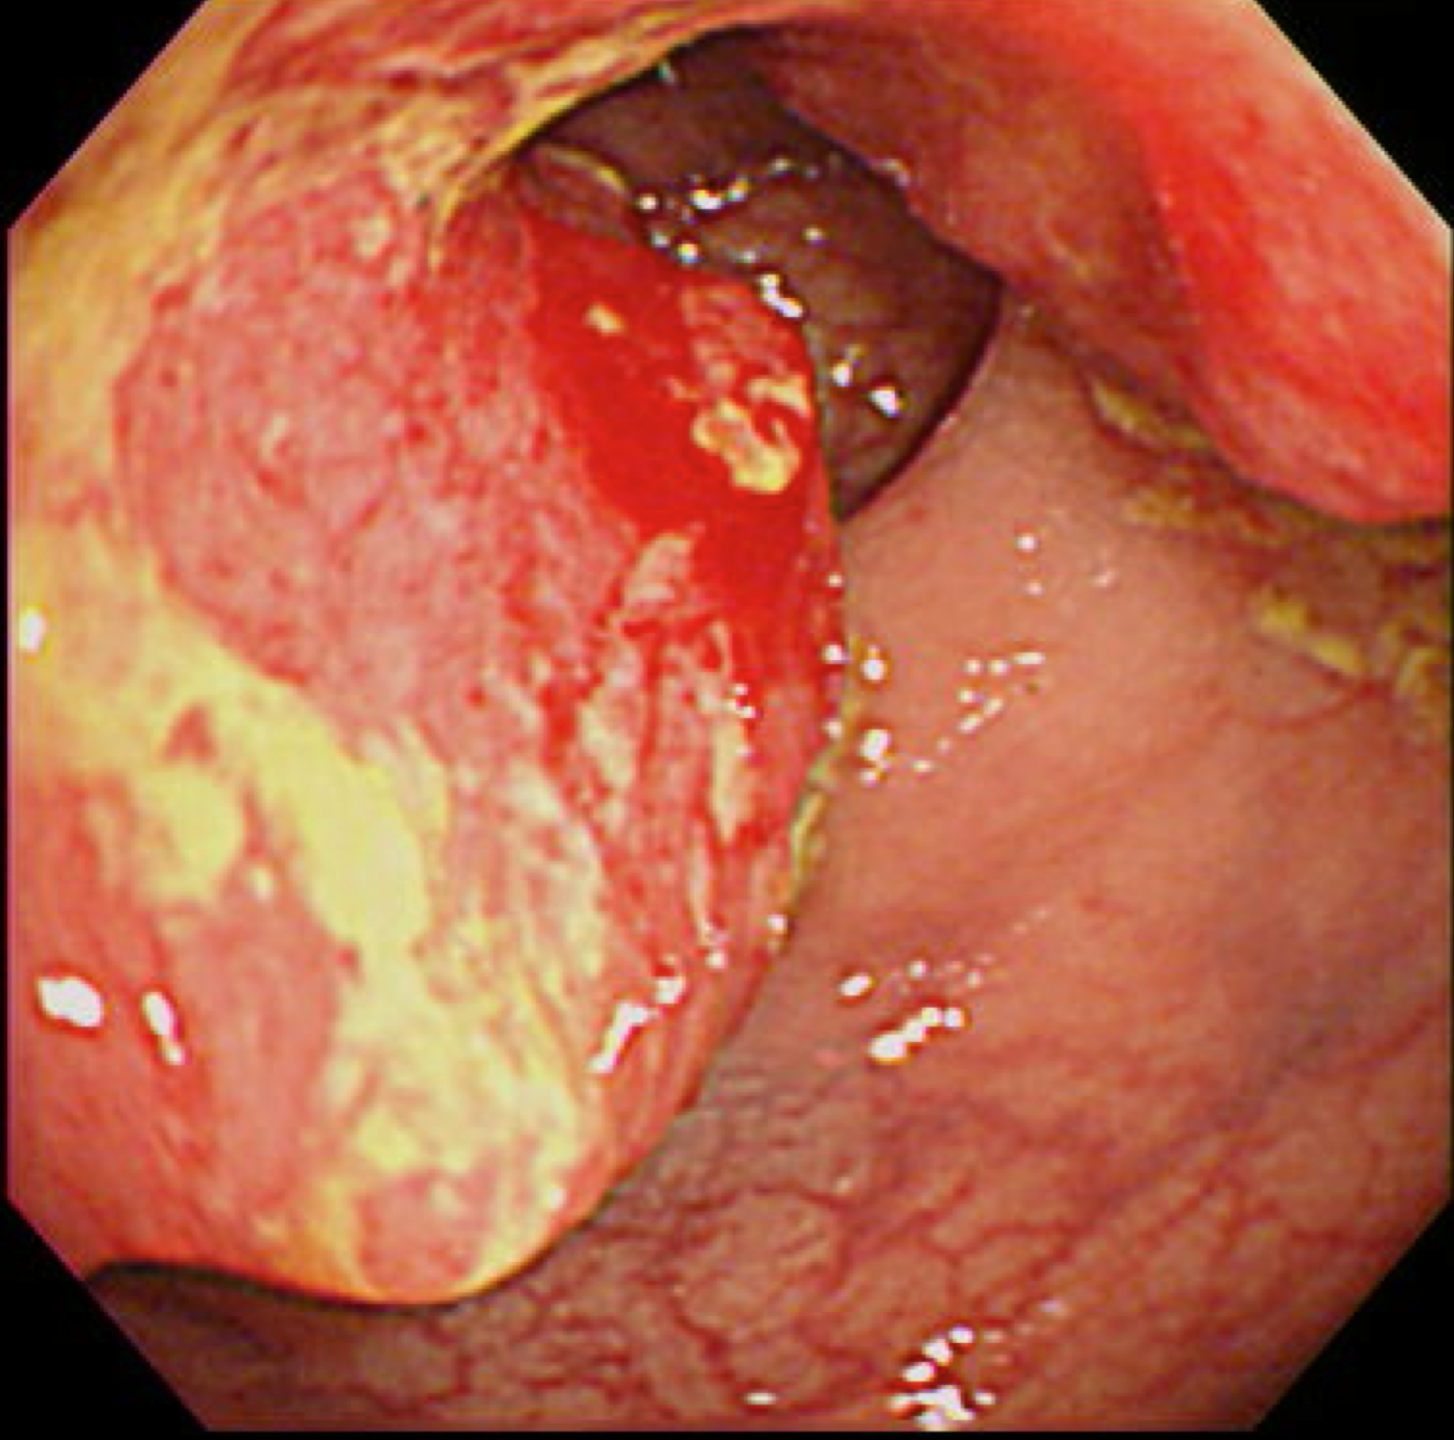

胃がん(上部消化管内視鏡)

胃がん検診

富山市の胃がん検診は胃内視鏡(上部消化管内視鏡)もしくは胃透視(バリウムを飲む検査)でおこなわれています。胃がんはかつては日本人にとって非常に多いがんでしたが、ヘリコバクターの保菌者の減少とともに、胃がんも少なくなりつつあります。

胃がん検診では喉頭部・食道・十二指腸上部を観察します。

当院では胃内視鏡(経口)のみを実施しております。胃の中を十分に検査するために高解像度の内視鏡を使用しており、そのため口からの内視鏡検査となります。一般的に鼻からの経鼻内視鏡による検査の方が楽な検査と言われていますが、内視鏡が細い分、最新型の経口高解像度内視鏡に比べて解像度が落ちます。

富山市からの検診の案内には経鼻内視鏡のできる施設が明示されていますので、ご希望に合わせて受診してください。